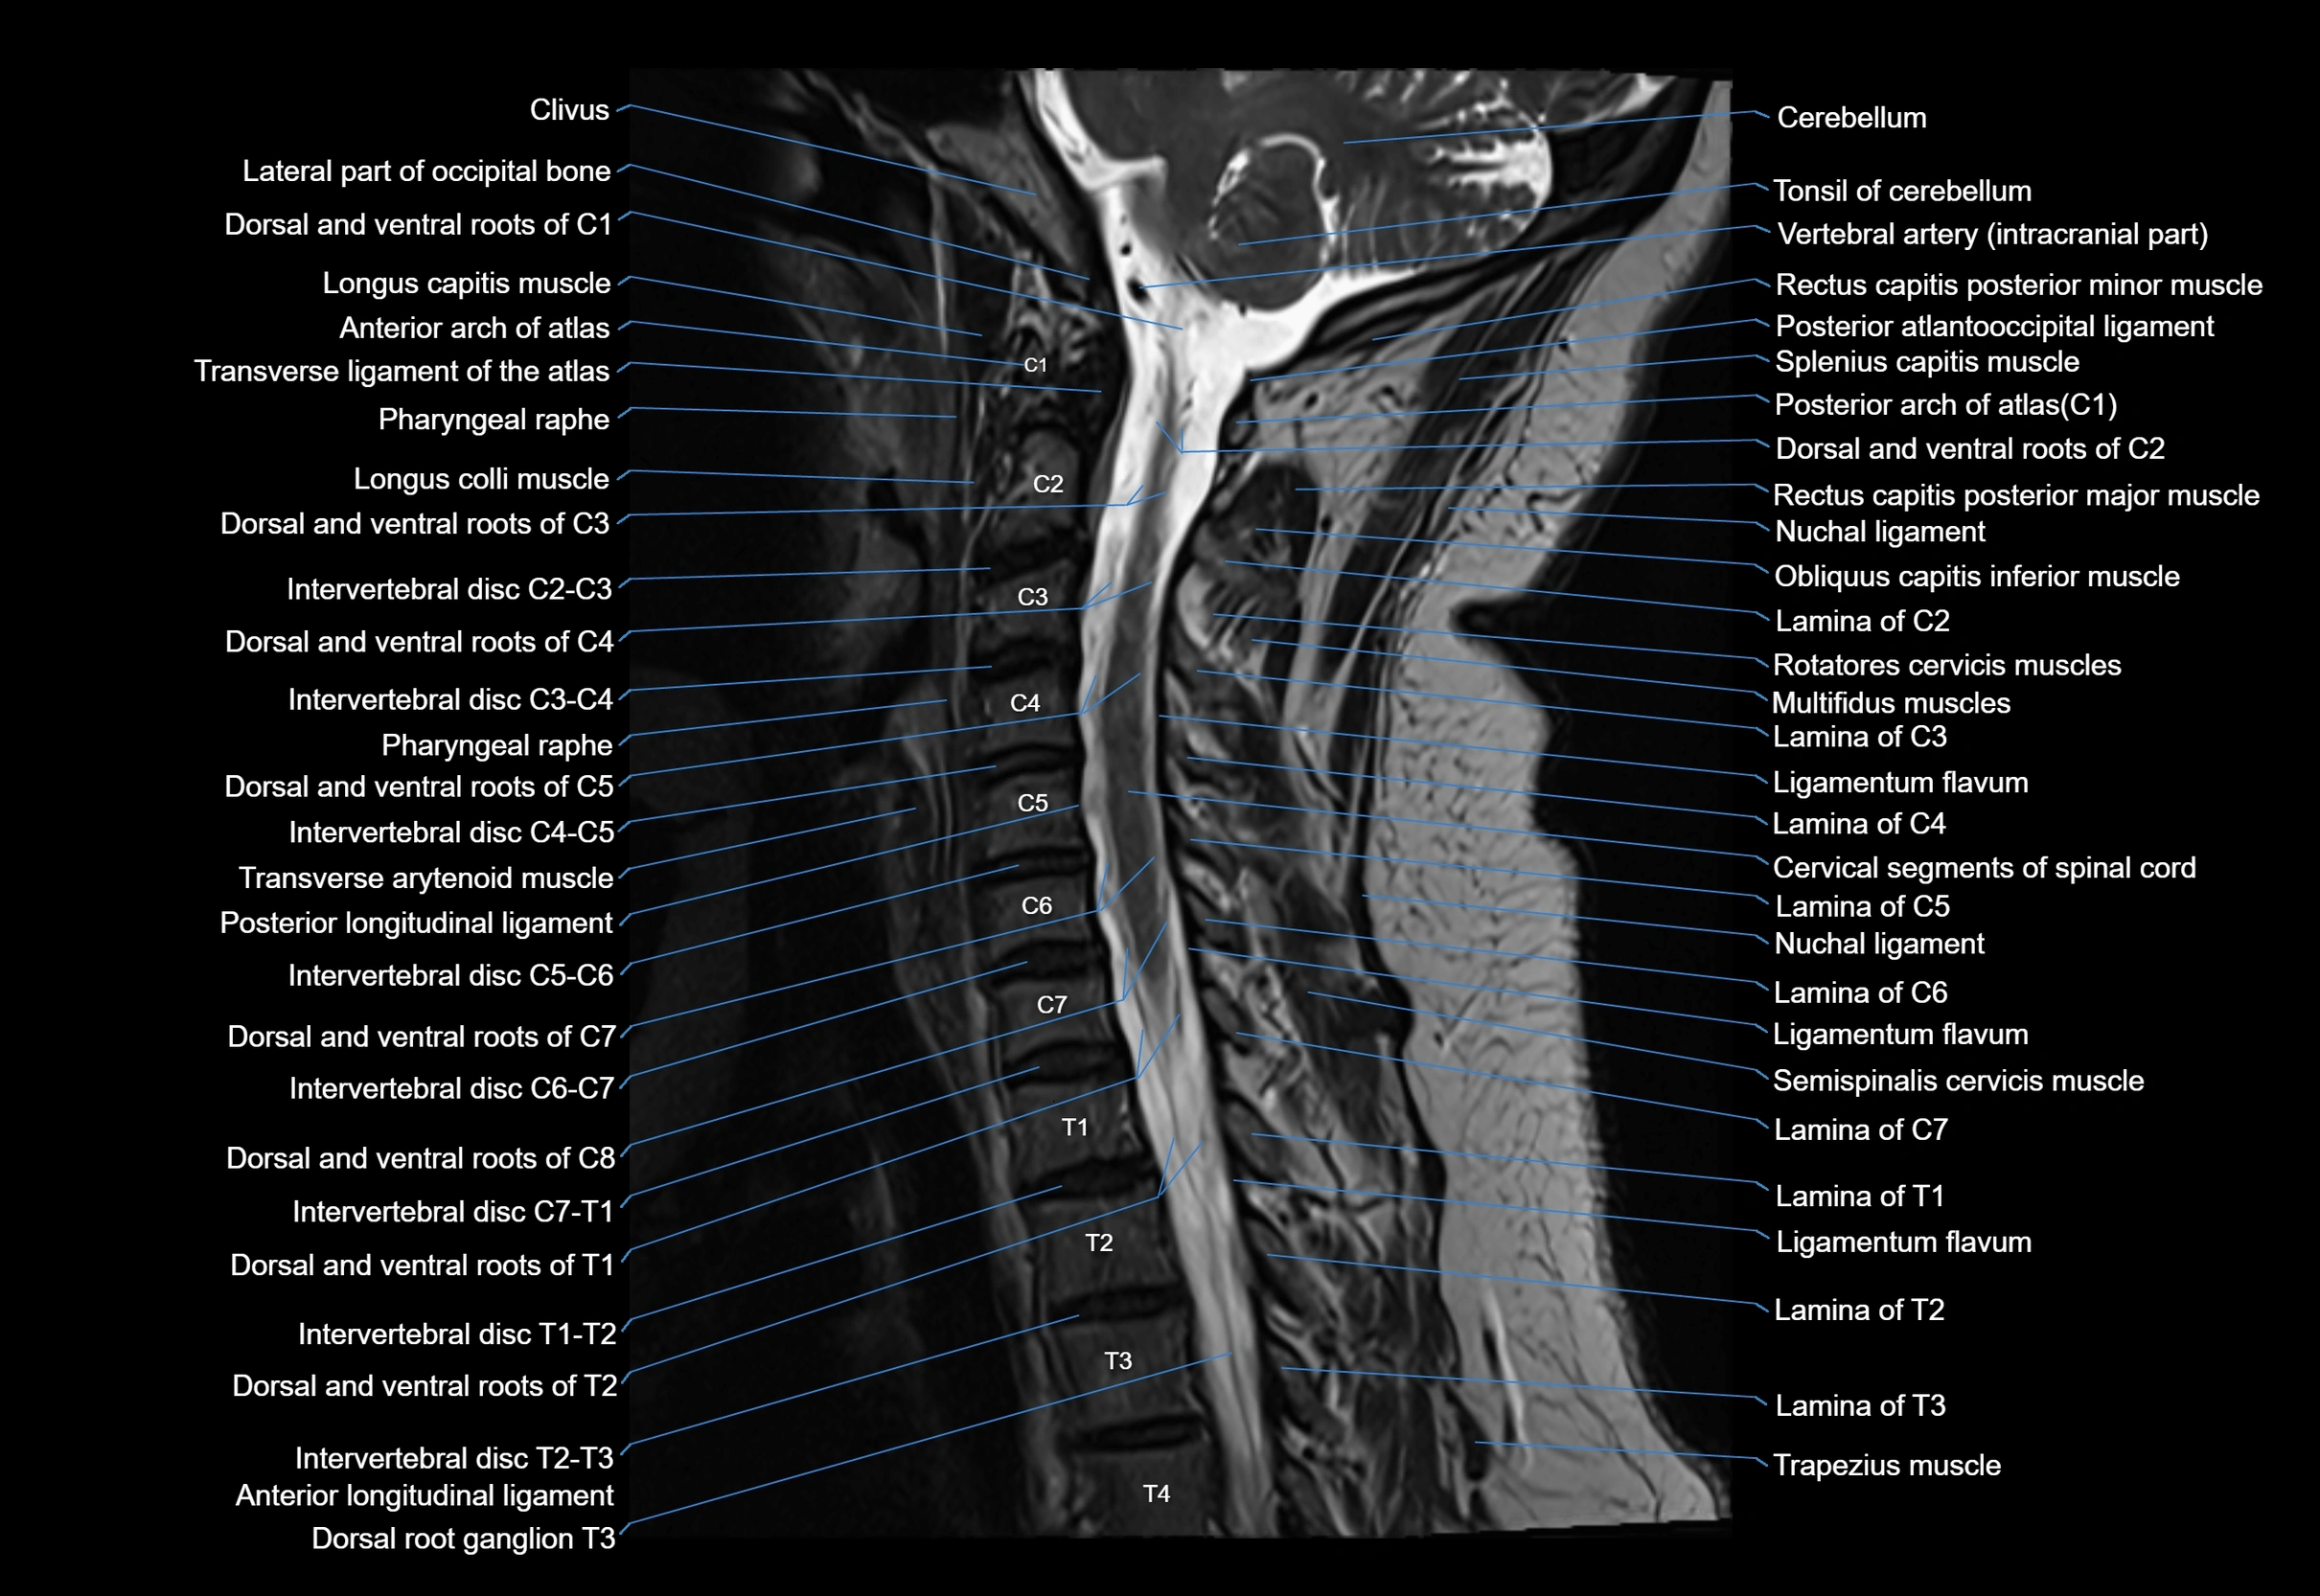

MRI image

image